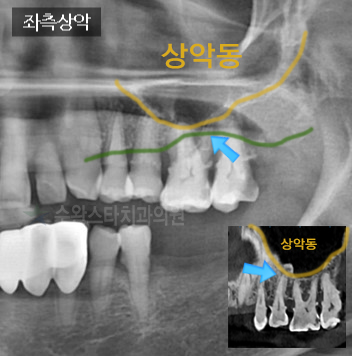

처음 내원 시 좌측 상악 파노라마 50대 여성(2024/3월 촬영)

x-ray 사진을 보게 되면,

주황색 선으로 그은 부분은

상악동이라는 빈 공간의

밑 라인입니다.

초록색 선은

환자분의 잇몸뼈(치조골)을 나타냅니다.